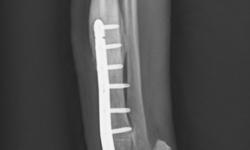

Pacient č.: 2. - pooperační rtg.

Pacient č. 2.

• Plemeno sheltie, pohlaví fena, stáří 6 let

• Příčina kulhání – úraz zápěstí z přetížení

• Diagnoza HEI – hyperextenzní poranění

• Terapie: PCA – pankarpální artrodéza